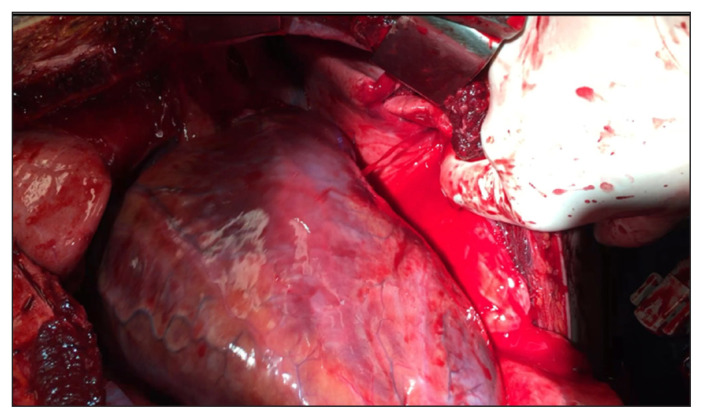

Atrial defects are repaired by placing a vascular clamp under the perforation (Figure 5). Preventing additional traction to the atrial wall is essential to avoid lacerating it. Simple, continuous stitches with 5–0 polypropylene sutures on an RB needle can be used. Alternatively, a 6–0 polypropylene suture may be employed if the atrial tissue is exceptionally thin. Running horizontal mattress stitches may be more appropriate for thin atrial walls, which require a technique that spreads tension along the entire wound edge.6 When the injury cannot be controlled with a single clamp, multiple Allis clamps can be engaged in a row to pinch the wound edges together, followed by mattress sutures underneath. If the atrium is especially dilated, pledget reinforcement may be required. When time is limited, or such bioprosthetic materials are not readily available, small pieces of the pericardium can also be used to buttress sutures.29 Two needles from a double-ended suture are passed through the pericardial sling on 1 side, then across the laceration, and out the opposite pericardial edge. Pledgets are cut and fashioned into a particular size and the 2 ends are pulled. The second pledget is apposed to the ventricular wound by irrigation, and then the sutures are tied to complete the stitch. This simple technique is also useful when small pledgets are required for vascular anastomoses and repairs (Figure 6).

Fig. 5.

Cardiac repair. Ventricular injury (shown from below). Ventricular injuries are often immediately controllable with digital pressure. Lacerations can be rapidly approximated in damage control situations with skin staples. Definitive repairs are often done with simple or horizontal mattress interrupted sutures, using 2-0 or 3-0 polypropylene sutures on MH-tapered 3/8 circumference needles.